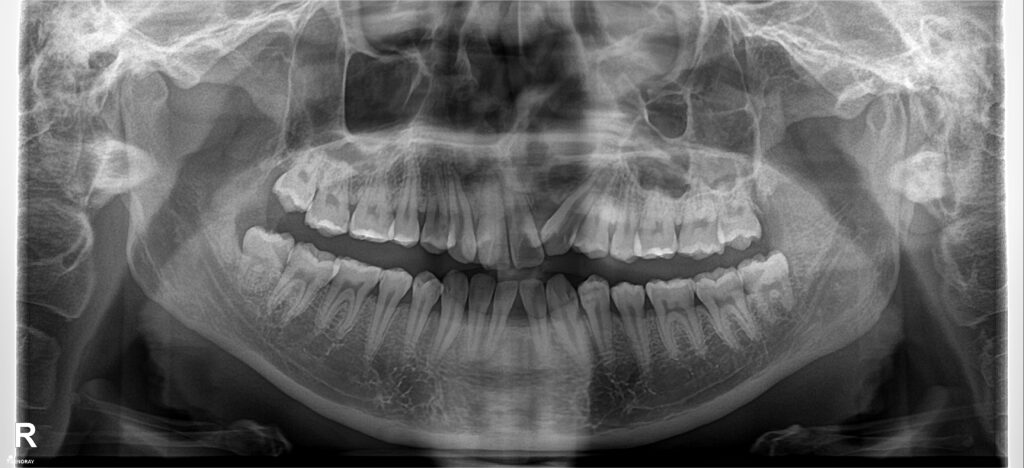

BN khớp cắn hạng 3, hàm trên nằm trọn trong hàm dưới. Hàm trên cực hẹp. Chỉ định nong hàm với ốc nong nhanh và dây Damon. Dựng trục răng 7 hàm dưới, torque lại trục răng hàm trên, giải “hẹp” hàm trên, kéo răng lệch phía khẩu cái ra ngoài. Giải khớp cắn ngược răng cửa, cắn kéo R7, tất cả dùng dây cung thẳng liên tục.